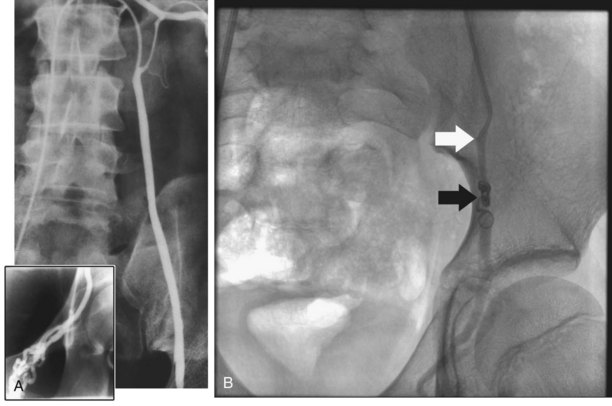

TRUS provides excellent definition of the prostate, seminal vesicles, ampulla of the vas deferens, and the ejaculatory ducts. TRUS is primarily employed to examine patients suspected to have ejaculatory duct obstruction (EDO). These patients usually have low-volume azoospermia (volume <1 mL) with acidic pH and negative semen fructose. TRUS typically employs the 5- to 7-MHz endocavitary probe with scanning in both the longitudinal and transverse planes. Careful examination of verumontanum may identify midline prostatic cysts such as müllerian or wolffian duct cysts or stones obstructing the ejaculatory duct (Fig. 21–2). Often the ejaculatory duct may not be well visualized, but dilation of the seminal vesicles serves as a de facto sign of ejaculatory duct obstruction. Although not always present with ejaculatory duct obstruction, seminal vesicle width in excess of at least 12 to 15 mm or ejaculatory duct diameter greater than 2.3 mm is considered suggestive of obstruction (Carter et al, 1989; Vazquez-Levin et al, 1994; Smith et al, 2008).

Figure 21–2 Transrectal ultrasound (sagittal image) demonstrating a dilated ejaculatory duct culminating in an ejaculatory duct cyst.

Seminal vesicle aspiration using a 20-gauge needle at the time of TRUS has been used to further increase the specificity of the diagnostic techniques. Significant quantities of sperm are not normally present in the seminal vesicles. Findings of three or more sperm per HPF in the seminal vesicle aspirate support the diagnosis of EDO (Jarow, 1994). Test accuracy is improved by performing aspiration within 24 hours of ejaculation (Jarow, 1996).

Seminovesiculography using transrectal injection of radioopaque contrast (50% renograffin) into the seminal vesicles under TRUS guidance with postinjection radiographs can provide excellent anatomic detail of the seminal vesicles and ejaculatory ducts. Seminal vesicle chromotubation is a variation of seminovesiculography using the injection of dilute indigo carmine or methylene blue (1:5 dilution with saline) into the seminal vesicles via TRUS guidance followed by cystoscopic inspection of the ejaculatory ducts in the prostatic urethra to confirm patency. The dynamic tests of chromotubation and seminal vesiculography offer higher specificity for detection of EDO than static TRUS imaging alone (Purohit et al, 2004). The newest adjunctive technique, ejaculatory duct manometry, involves hydraulic assessment of the ejaculatory ducts at the time of seminal vesicle chromotubation, noting that men with EDO have higher mean ejaculatory duct opening pressures, 116 cm H2O versus 33 cm H2O in fertile controls (Eisenberg, 2008). Despite these advances in diagnostic techniques, criteria for diagnosis of complete EDO remain unclear and those for partial EDO remain controversial.